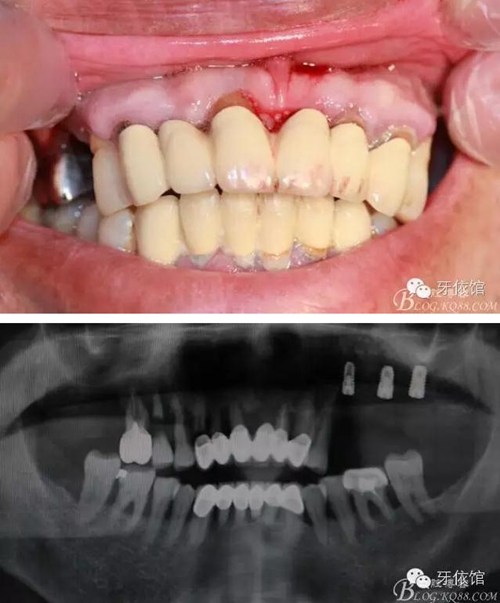

患者男,65歲,口內(nèi)多組烤瓷橋,具體時間不詳,左上5,6,7已于5個月前即可種植,OSS-TEM系統(tǒng),余留牙都已三度松動;此患者笑線高,微笑時唇緣在齦緣上4mm。

術(shù)前口內(nèi)照和X光片